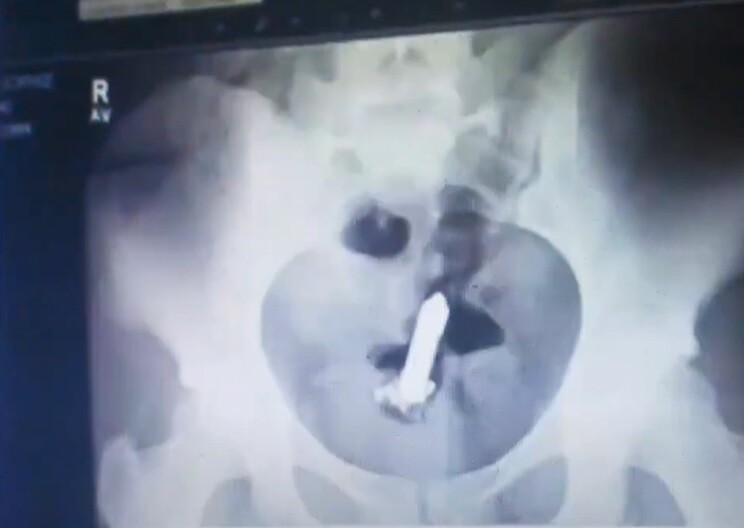

“Me tocó dormir con el objeto vibrando porque estaban mis hijos al lado”, confesó la mujer. Una curiosa anécdota fue revelada por parte de una tiktoker...